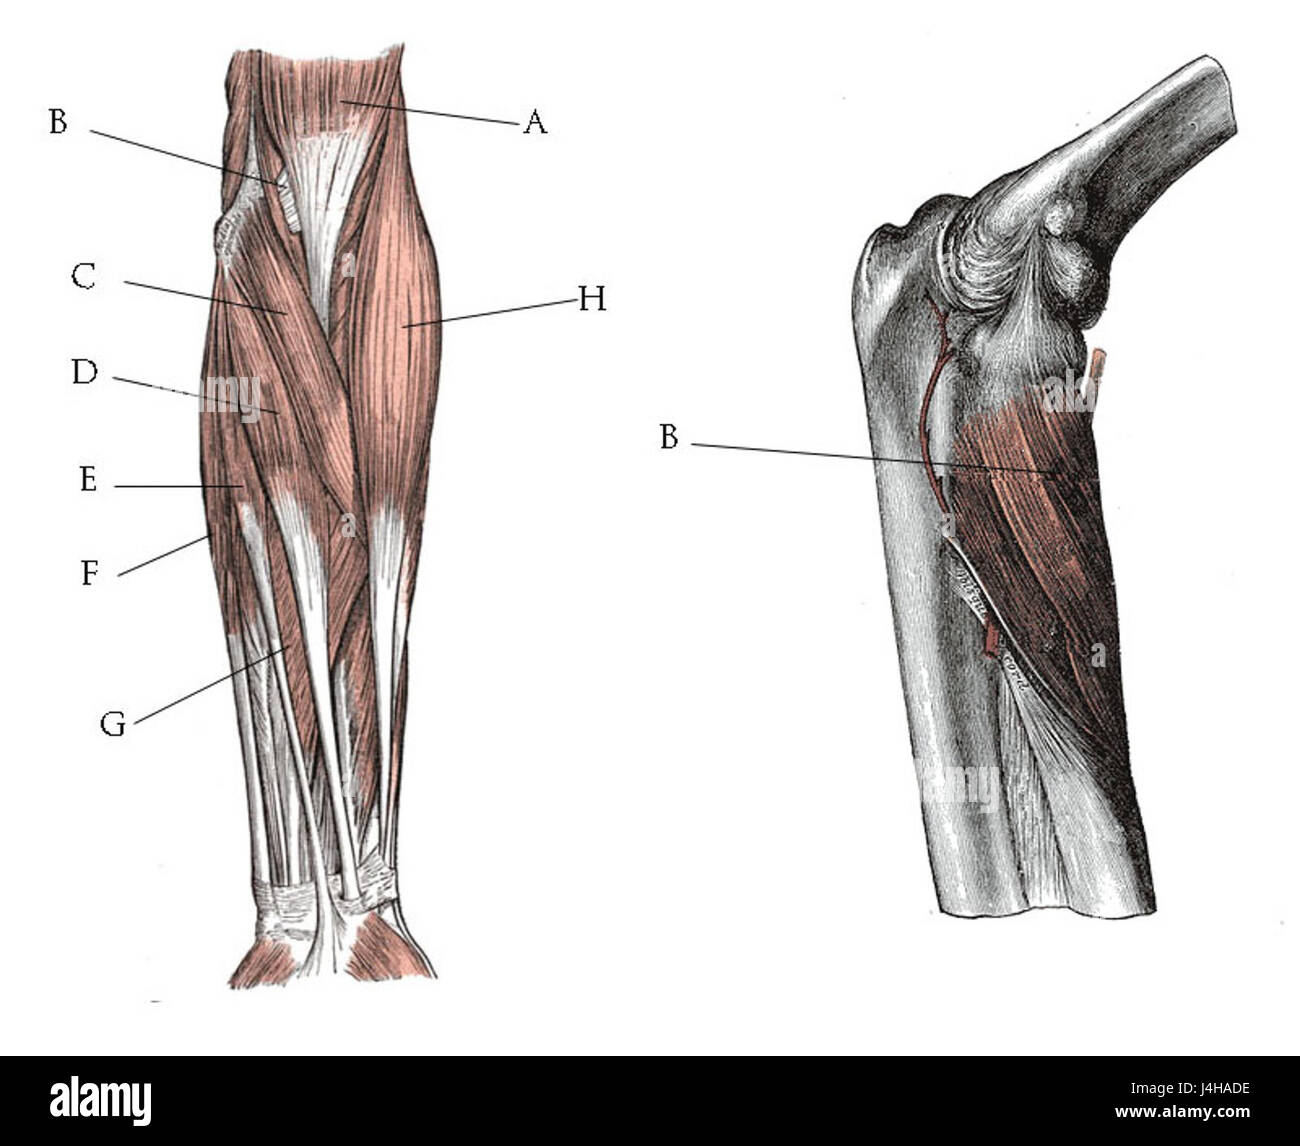

RF2BTGJYJ–Der Humerus ist ein langer Knochen des oberen Gliedes zwischen Ellenbogengelenk und Schulter, Vintage-Linie Zeichnung oder Gravur Illustration.

RF2BTHB20–Der Humerus ist ein langer Knochen des oberen Gliedes zwischen Ellenbogengelenk und Schulter, Vintage-Linie Zeichnung oder Gravur Illustration.